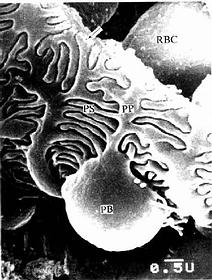

兔肾小体扫描电镜像

图15-7 兔肾小体扫描电镜像 示足细胞

PB足细胞体,PP初级突起,PS次级突起,RBC红细胞

↑基膜(河北医学院电镜供图)